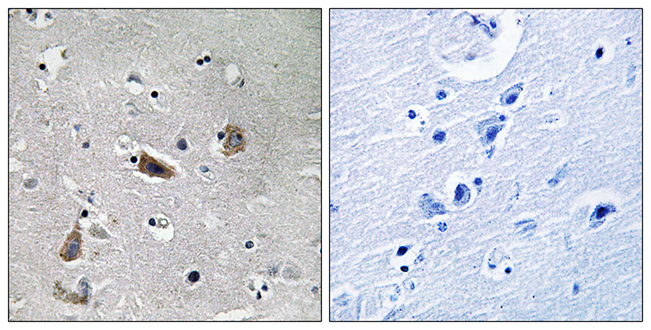

ApplicationsELISA, ImmunoHistoChemistry

ReactivityHuman, Mouse, Rat

ApplicationsELISA, ImmunoHistoChemistry

ReactivityHuman, Mouse, Rat

ApplicationsELISA, ImmunoHistoChemistry

ReactivityHuman, Mouse, Rat

ApplicationsELISA, ImmunoHistoChemistry

ReactivityHuman, Mouse, Rat